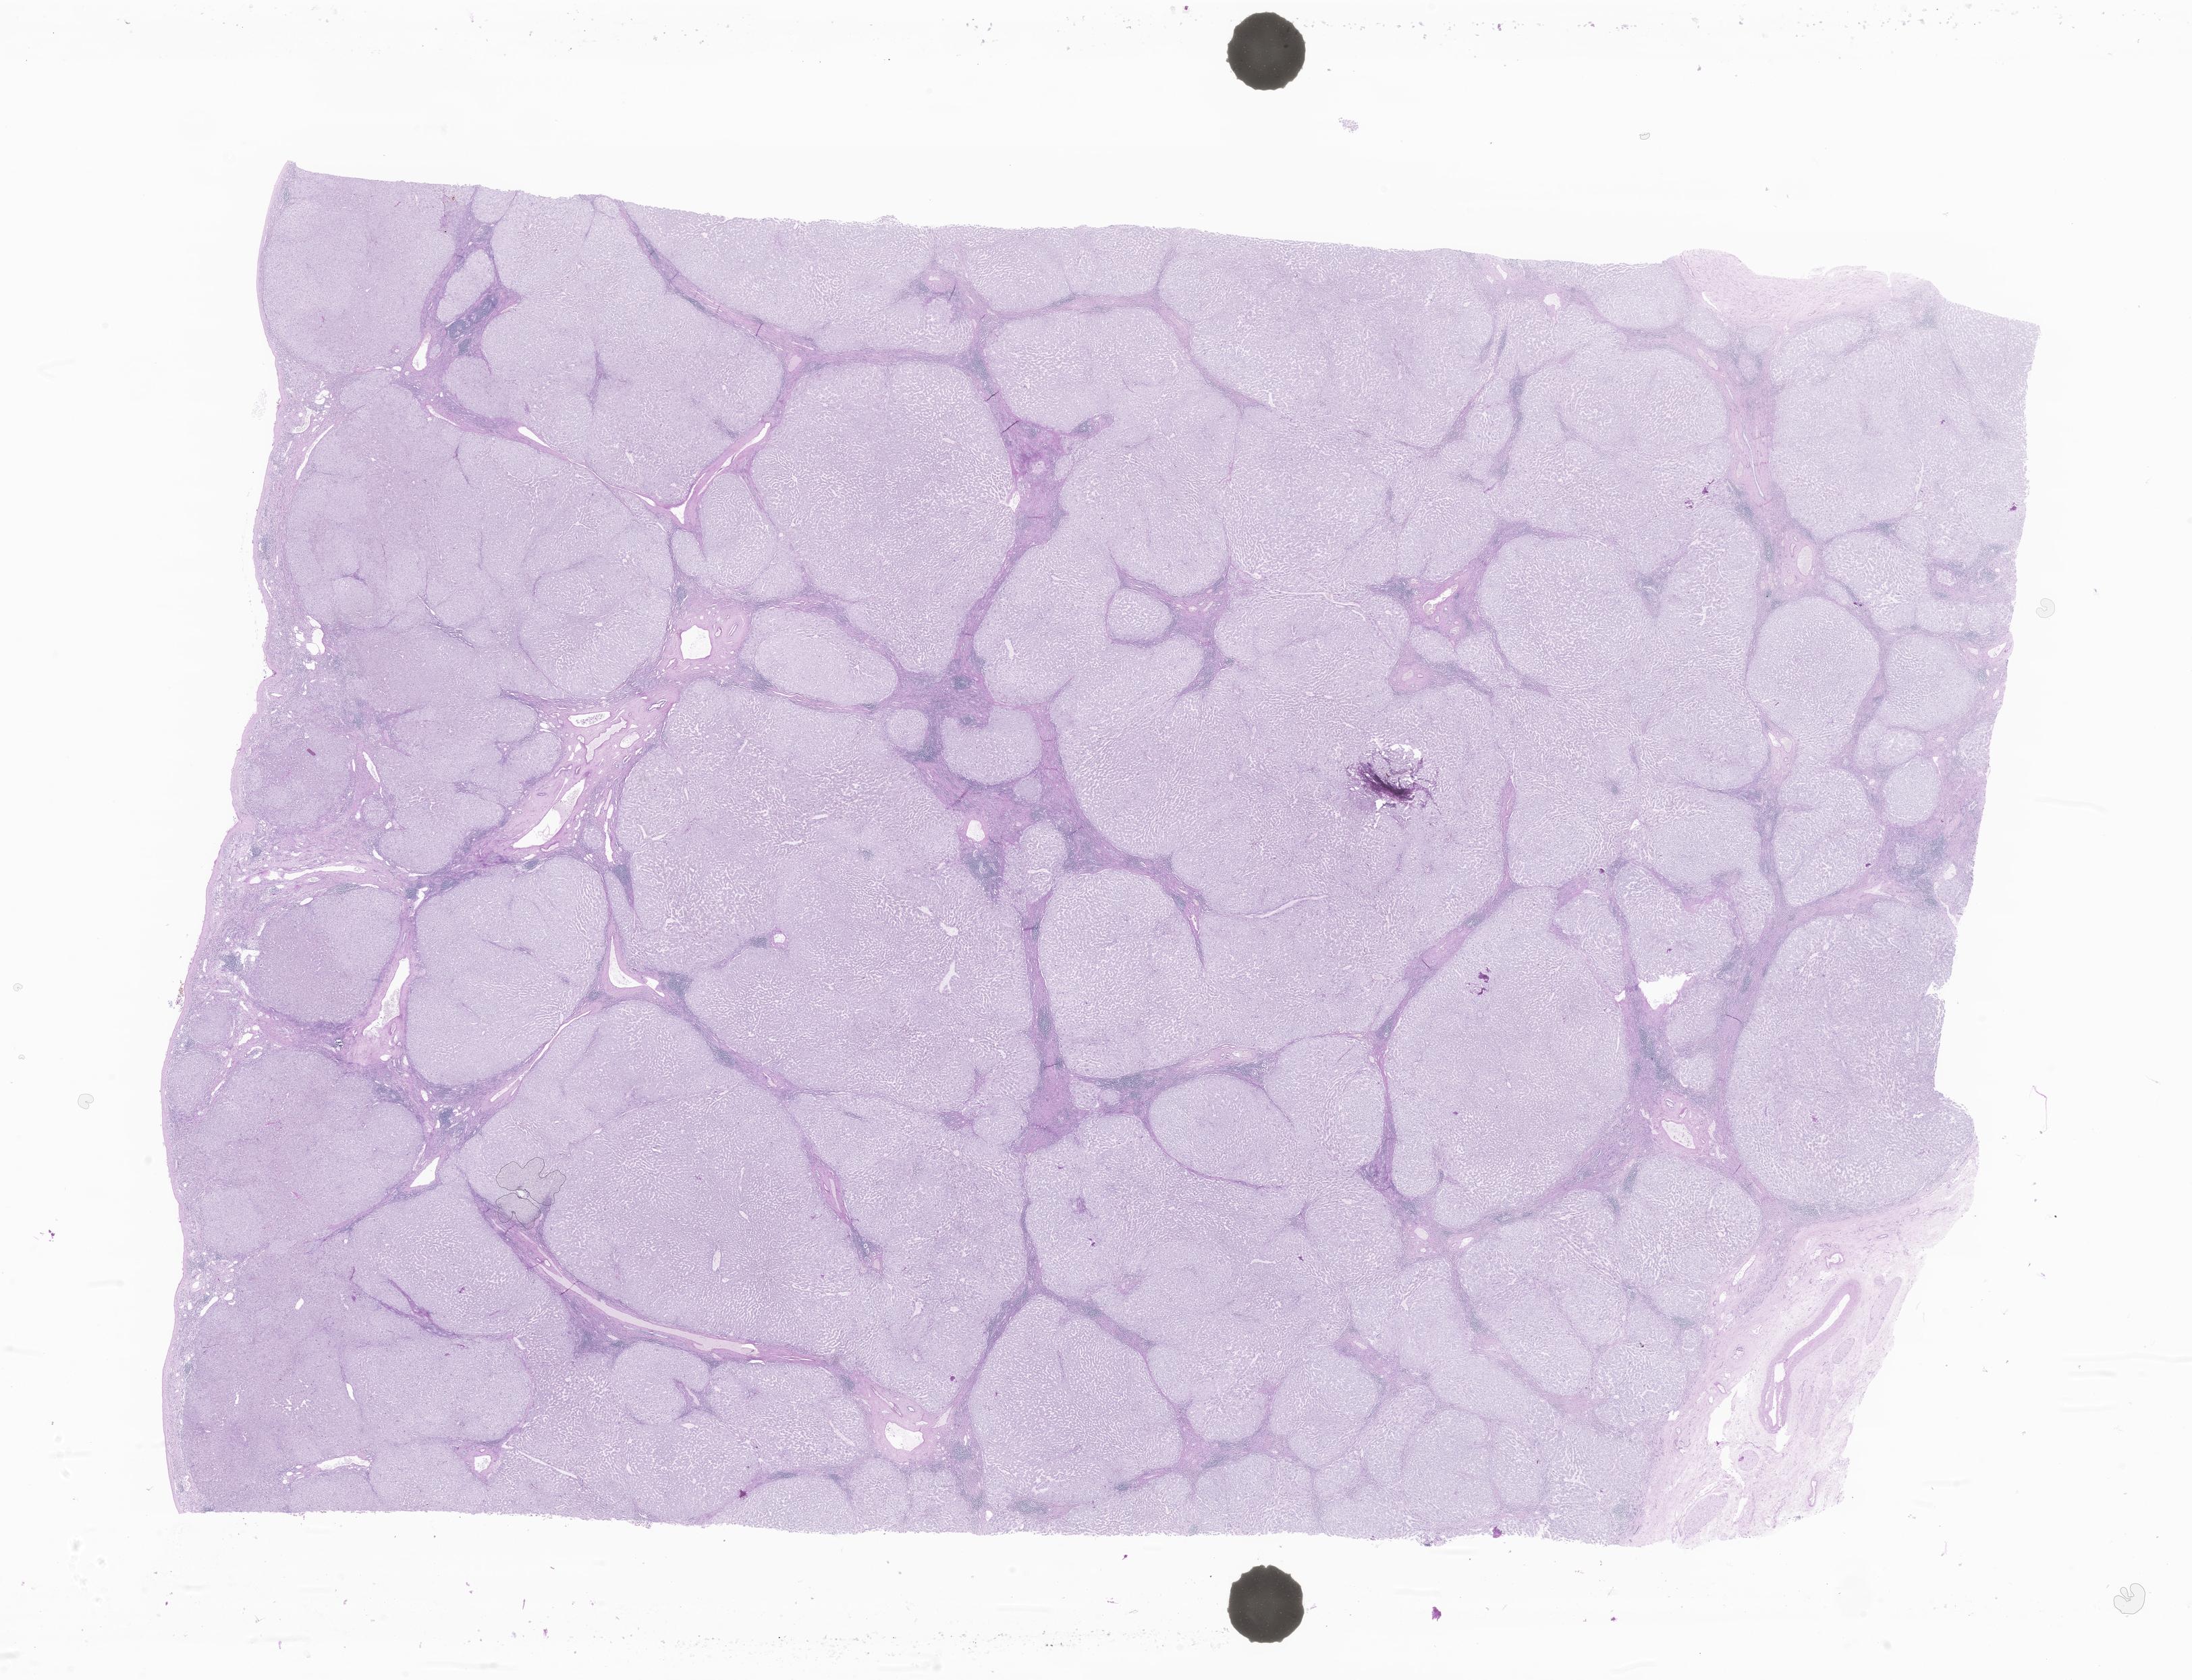

This dataset contains anonymised whole slide images (WSIs) of human liver received during routine clinical practice, comprising a variety of benign and malignant diagnoses. This dataset includes biopsies and surgical resection specimens, from both native and transplant liver specimens along with any associated specimens (e.g. gallbladder). It includes a mixture of non-targeted/medical and tumour (primary or metastatic) specimens and gallbladder specimens. All cases include a H&E stain along with any additional histochemical or immunohistochemical stains where available.

Cytokeratin Associated Marker 5.2 P63 Immunohistochemical (IHC) staining for CD56 Ziehl-Neelsen stain (SP or TB infection) Immunohistochemical (IHC) staining for Ki-67 P53-DO7 Wade-Fite Prostate Specific Antigen Glypican-3 CytoKeratin 7 Alcian Blue (AB) - Periodic Acid-Schiff (PAS) - Hematoxylin (H) Estrogen Receptors CarcinoEmbryonic Antigen (Monoclonal) CarcinoEmbryonic Antigen Polyclonal Alpha-Synuclein Wilms tumor Hepatitis B surface antigen Shikata Orcein stain Discovered On GIST 1 Hepatitis B Core Antigen Martius Scarlet Blue Immunohistochemical (IHC) staining for CD20 GLUcose Transporter Immunohistochemical (IHC) staining for caudal-related homeobox gene 2 Periodic Acid-Schiff with Diastase Sudan IV Immunohistochemical (IHC) staining for CD31 P16 Antihuman Epithelial Antigen Hep Par1 Antibody C4d Cancer Antigen 125 Immunohistochemical (IHC) staining for CD34 Immunohistochemical (IHC) staining for CD68 Programmed Cell Death Ligand 1 Reticulin Gram Cytokeratin AE1/AE3 Melanoma A B-Catenin CytoKeratin 20 MNF116 CytoKeratin 5 and 6 Synaptophysin Immunohistochemical (IHC) staining for CD45 Periodic Acid-Schiff Human Melanoma Black 45 Immuno Spare Hematoxylin and Eosin CytoKeratin 5 Gross Cystic Disease Fluid Protein-15 Perls (Iron) Thyroid Transcription Factor-1 Progesterone Receptor A Prostatic Acid Phosphatase Elastic Van Gieson Immunohistochemical (IHC) staining for CD3 S100 protein Cancer Antigen 19-9 CytoKeratin 19 CytoKeratin 8 and 18 Hematoxylin and Eosin Frozen CytoMegaloVirus PAX-8 Rhodanine Grocott's Methenamine Silver Amylase Alpha Masson Fontana Chromogranin A Human Epidermal Growth Factor Receptor 2 Myeloperoxidase Glutamine Synthetase Alpha-FetoProtein Van Gieson Sudan IV Defat Congo Red |